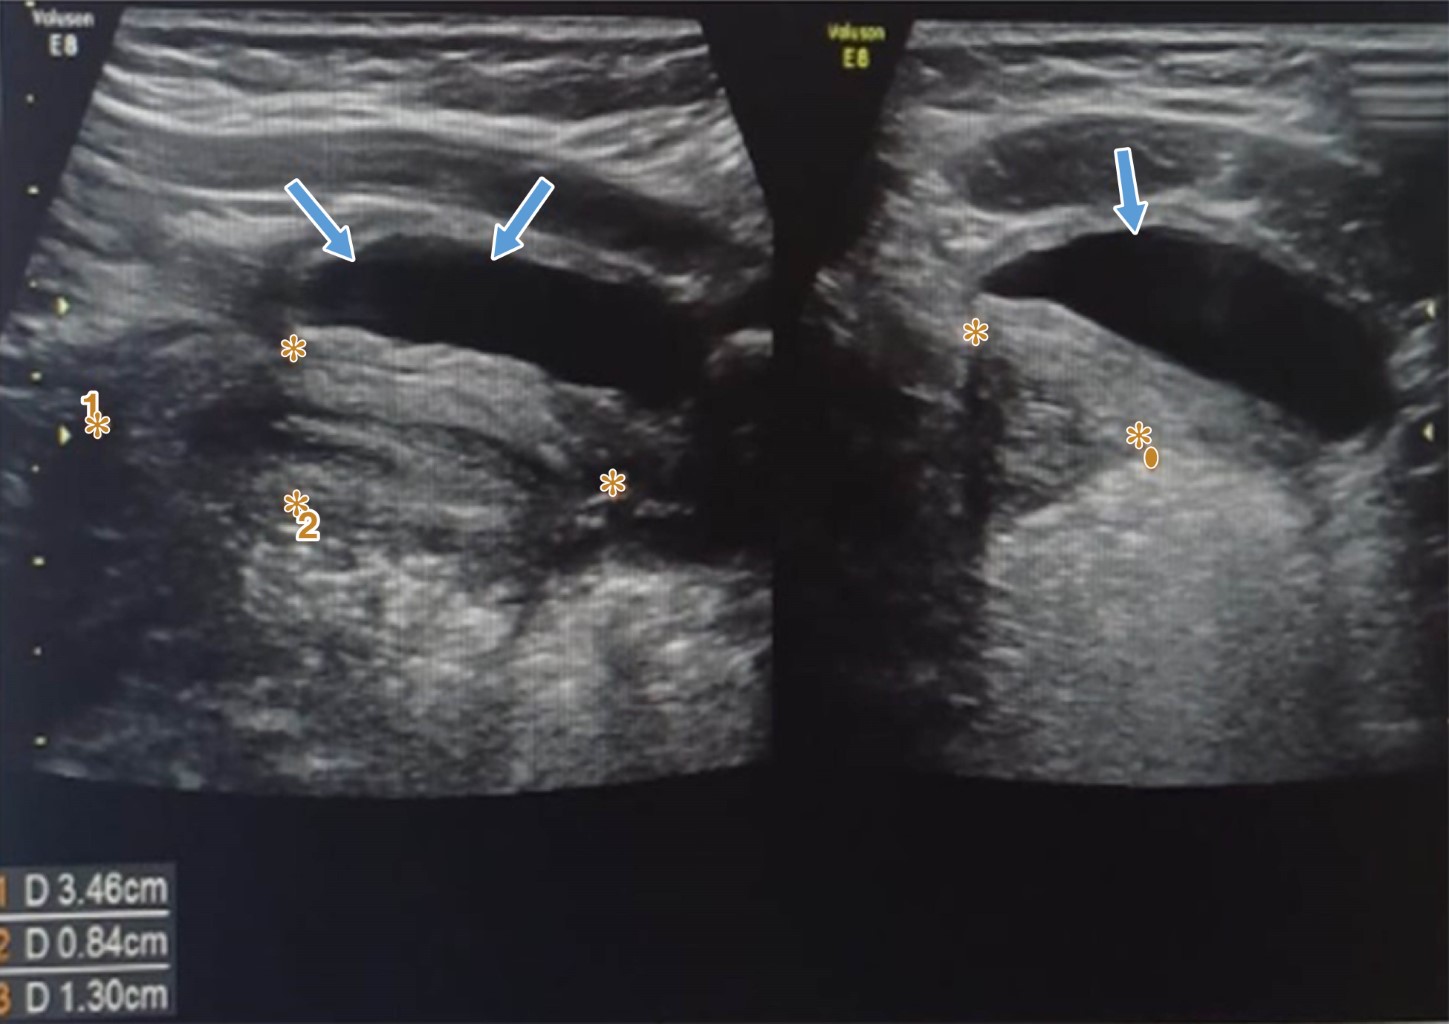

Por lo anterior, se solicitó ultrasonido abdominal, en el cual el ovario izquierdo tenía dimensiones de 51 × 39 × 41 mm, con una imagen quística bien definida, con volumen de 42.5 mL. Ovario derecho y útero normales (Figura 1). Tomografía de abdomen: tumor quístico posiblemente de ovario, sin captación ni realce en fase contrastada, tamaño de 5.7 × 5.2 × 7 cm.

Figura 1